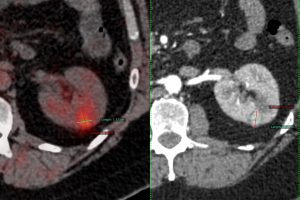

As with any ablative technique, the cryoprobe is guided into the tumor using CT and CT fluoroscopy and then depending on the size, the ablation is performed for a specific period of time. While cryoablation has been used for larger than 4 cm lesions, mainly for palliation, it is best suited for < 4 cm sized lesions, especially in single kidneys (Fig. 1), where the extent of renal damage can be controlled and where the extent of nephron sparing is better than with surgery.